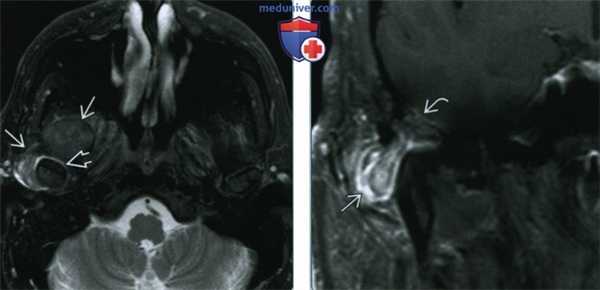

(Слева) На аксиальной МРТ (Т2 ВИ FS) у пациента с болезнью накопления КПФД вокруг компонентов правого ВНЧС визуализируется неоднородное объемное образование с преимущественно гипоинтенсивным сигналом. Обратите внимание на гиперинтенсивную жидкость в суставном пространстве вокруг мыщелка нижней челюсти.

(Справа) На корональной MPT (Т1 ВИ С+) у этого же пациента определяется контрастное усиление объемного образования в нижних наружных отделах. Обратите внимание на дефект крыши суставной ямки и легкое контрастирование твердой мозговой оболочки. Интракраниальное распространение отсутствует.

(Слева) При МРТ Т2ВИ FS в аксиальной проекции у пациента с болезнью депонирования кальция пирофосфата возле правою височно-нижнечелюстного сустава визуализируется патологический участок с неоднородным, преимущественно гипоинтенсивным сигналом. Наблюдается жидкость в суставном пространстве вокруг головки мыщелка нижней челюсти.

(Справа) При МРТ Т1ВИ FS с КУ в корональной проекции снизу и снаружи визуализируется объемное образование, накапливающее контраст. Отмечается дефект кости, формирующей суставную ямку, и легкое контрастное усиление твердой мозговой оболочки; но явные признаки распространения процесса в полость черепа отсутствуют.